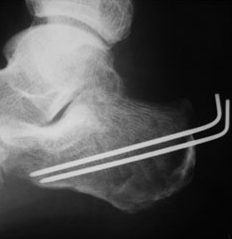

중족골은 발의 5개로 이루어진 뼈로 몇 번째 뼈가 골절되느냐에 따라 앞에 숫자가 붙습니다. 제5중족골은 새끼발가락 쪽 뼈에 해당합니다. 보행 중 바닥의 단차로 안쪽으로 발이 비틀렸을 때 자주 일어나며, 뼈의 어긋남이 없는 골절은 깁스로 고정하거나 압박붕대로 고정하는 등의 보존치료등을 시행하며, 어긋남의 편차가 크다면 강선과 와이어 등으로 고정하는 수술을 하게 될 가능성이 있습니다.